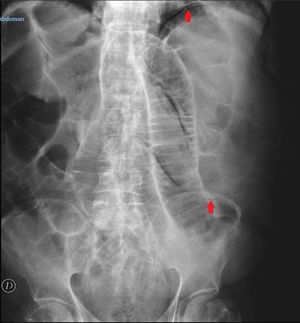

An 82-year-old man presented with bloating and generalized abdominal pain, accompanied by vomiting (dark in color, with an aspect of retention vomiting) and diarrheic stools. A plain abdominal x-ray (Fig. 1) showed air in the gastric wall and bowel segment dilation. An abdominal computed tomography (CT) scan was ordered (Fig. 2) that revealed intramural gas associated with gastric dilation, pneumoperitoneum (Fig. 3), and gas in the portal vein (Fig. 4). An exploratory laparotomy was performed, finding a distended stomach with gas bubbles in its serosa and no signs of transmural necrosis or perforation. Intraoperative gastroscopy identified ulcerated-necrotic mucosa with no spontaneous bleeding on the posterior surface, body, and greater curvature. Given those findings, no further surgical act was carried out. Lactobacillus jensenii was isolated in blood cultures and treated with meropenem + linezolid. The patient progressed favorably, with improvement in the control abdominal CT scan, and was released from the hospital. Emphysematous gastritis is a rare pathology produced by the translocation of gas-producing microorganisms in the walls of the stomach. The causal agent cannot be isolated in up to 42.4%1 of cases and there is a 60% mortality rate.2 CT is the diagnostic study of choice and is essential for making early diagnosis and implementing the vital support treatment with broad-spectrum antibiotics. Surgery is only required if there is no response to conservative treatment or in cases of severe sepsis or gastric perforation.3